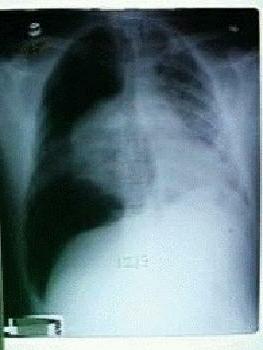

Her latest CXR shows severe bilateral airspace disease.